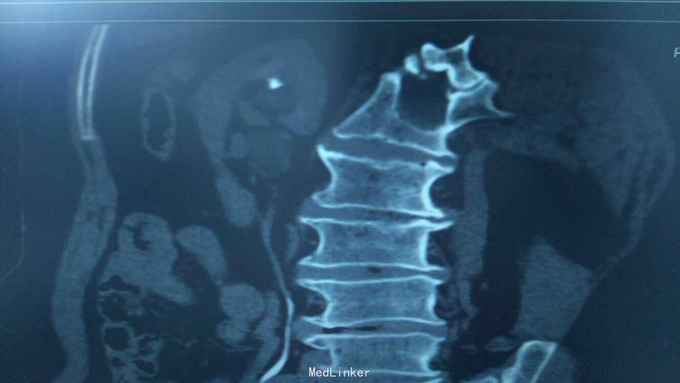

68岁,女性。 主诉:左侧腰痛1年,加重1个月。 病史:1年前无明显诱因出现左侧腰痛,无恶心呕吐,无肉眼血尿。1个月前加重,于外院查泌尿系彩超显示:左肾积液,输尿管显示不清。

诊断:双肾盂旁囊肿 治疗:因患者肾盂未明显受压,疼痛症状不明显,等待观察,暂未予处理。

双侧同时出现的病例并不多见,临床只能通过泌尿系统CTU或增强CT加以鉴别,彩超无法区分肾盂积水及盂旁囊肿。